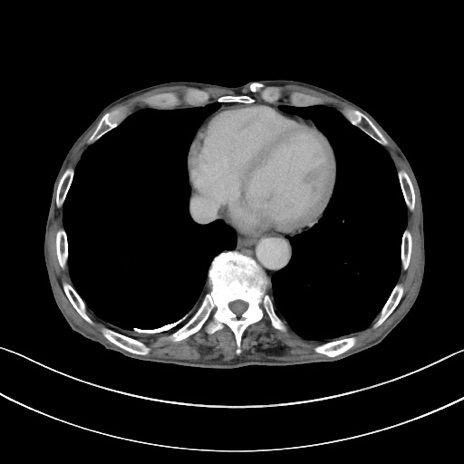

症例3(横断像)

【症例】 70歳代男性

【主訴】右鼠径部腫瘤、疼痛

【現病歴】本日朝より上記主訴あり、受診。

【既往歴】膀胱癌にて膀胱全摘、両側尿管皮膚瘻

【データ】WBC 5600、CRP 0.56